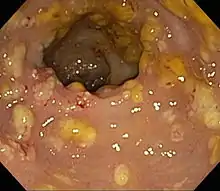

Prior to the advent of tests to detect C. difficile toxins, the diagnosis most often was made by colonoscopy or sigmoidoscopy. The appearance of "pseudomembranes" on the mucosa of the colon or rectum is highly suggestive, but not diagnostic of the condition.[45] The pseudomembranes are composed of an exudate made of inflammatory debris, white blood cells. Although colonoscopy and sigmoidoscopy are still employed, now stool testing for the presence of C. difficile toxins is frequently the first-line diagnostic approach. Usually, only two toxins are tested for—toxin A and toxin B—but the organism produces several others. This test is not 100% accurate, with a considerable false-negative rate even with repeat testing.[46]

| Pathological specimen showing pseudomembranous colitis | |